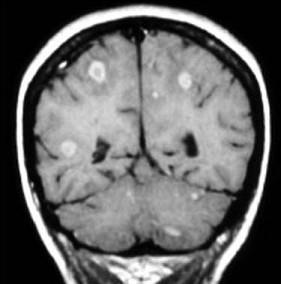

根据MRI表现,考虑为何种疾病 ( )A、海绵状脑病B、Lyme病C、脑弓形体病D、隐球菌性脑膜炎E、淋巴瘤

问题 根据MRI表现,考虑为何种疾病 ( )

选项 A、海绵状脑病 B、Lyme病 C、脑弓形体病 D、隐球菌性脑膜炎 E、淋巴瘤

答案 C